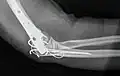

Bei Erwachsenen bedeuten perkondyläre Frakturen, dass die Trochlea humeri mit den Epikondylen nicht nur vom Schaft getrennt, sondern auch in sich, in zwei oder mehr Teile, gebrochen ist. Die operative Versorgung ist aufwändig: Der Nervus ulnaris muss freigelegt, das Olecranon durchsägt und mit dem Musculus triceps brachii hochgeklappt werden. Wie ein dreidimensionales Puzzle wird die Kondylenrolle rekonstruiert und mit Kirschner-Drähten und Kleinfragment-Lochschrauben zusammengehalten. Mit Drittelrohr- oder Rekonstruktionsplatten an beiden Seiten wird die (übungsstabile) Verbindung zum Schaft wiederhergestellt. Gut geeignet, aber teuer sind anatomisch vorgeformte winkelstabile Platten (Mayo). Das Olecranon wird mit einer Zuggurtung refixiert. In Hinblick auf die komplexe Anatomie des unteren Humerusendes sollte man sich bei der Rekonstruktion ein Humerusmodell zur Seite legen.

-

Doppelte Plattenosteosynthese